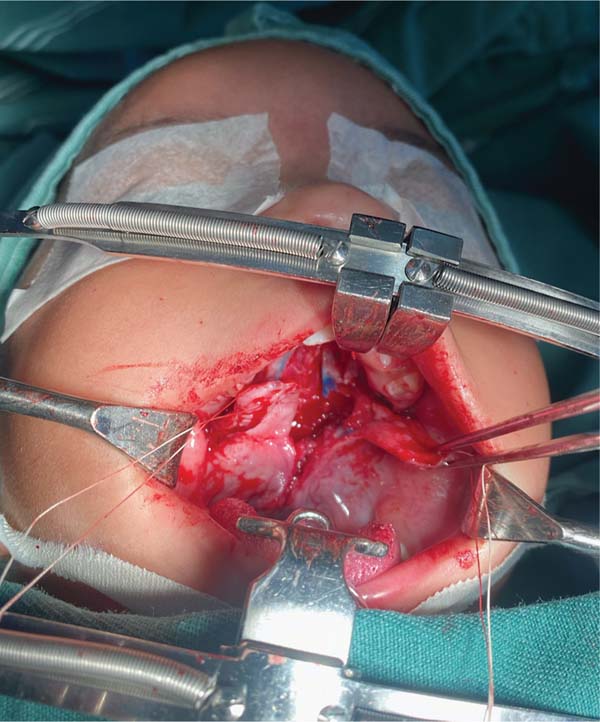

The new surgical tactic was designed to reduce suture tension in Pittsburgh’s zone III, where 50% of fistulas occur. This zone is a transitional area between the hard and soft palates, with thin tissues usually sutured in two planes, one in the nasal mucosa and the other in the oral mucosa. The proposed method introduces a third suture plane in the periosteum, a tissue more resistant to traction, with one or two U-shaped Vicryl-4.0 sutures (►Figs. 1–3).

The palatoplasty was performed under general anesthesia using the two-flap mucoperiosteal technique with intravelar veloplasty, following the principles of Sommerland41 and using lateral relaxing incisions. We applied sutures to the nasal mucosa and muscles, introducing a third suture plane in the transition zone, that is, using one to two U-shaped sutures in the periosteal plane in the distal portion of the mucoperiosteal flap. Then, we closed the oral mucosa and placed hemostatic material in the bloody areas. The patients received a liquid diet for 7 days and had no hand or arm movement restrictions.